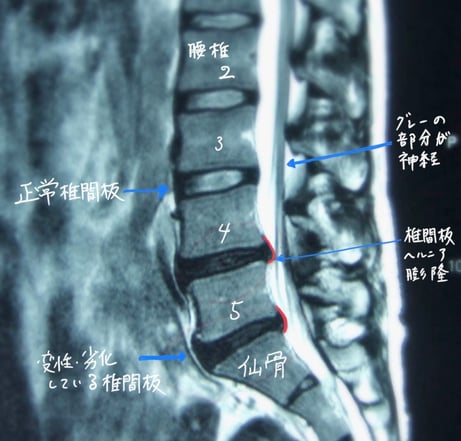

椎間板変性/椎間板ヘルニア

MRI(T2強調画像)では、正常な椎間板は白く写りますが、椎間板症では黒く写ります。

この画像は私の腰椎のもので、椎間板変性症と椎間板ヘルニアの兆候が見受けられます。

画像から、フラットバック、すなわち直線的な腰椎の配列が確認できます。(首でいうストレートネック)

重力負荷をダイレクトに受けてしまっていて、理想では少し前に弯曲(前にカーブ/この画像では左が前)することで重力の負荷を逃がすことが重要になります。

下2つの椎間板は色が黒く、変性の兆候が見られます。これは水分が減少して、劣化、萎縮して硬くなり、椎間板の質が低下していることを表しています。

上の3つの椎間板と比較すると、その差異が明確に見てとれ、薄く黒くなり後方へ出ているのが確認できます。

画像上では、馬尾神経に触れているようにも見受けられます。

このMRI画像は25年程前のものなので、現在の状態はもう少し進行している可能性が十分に考えられます。